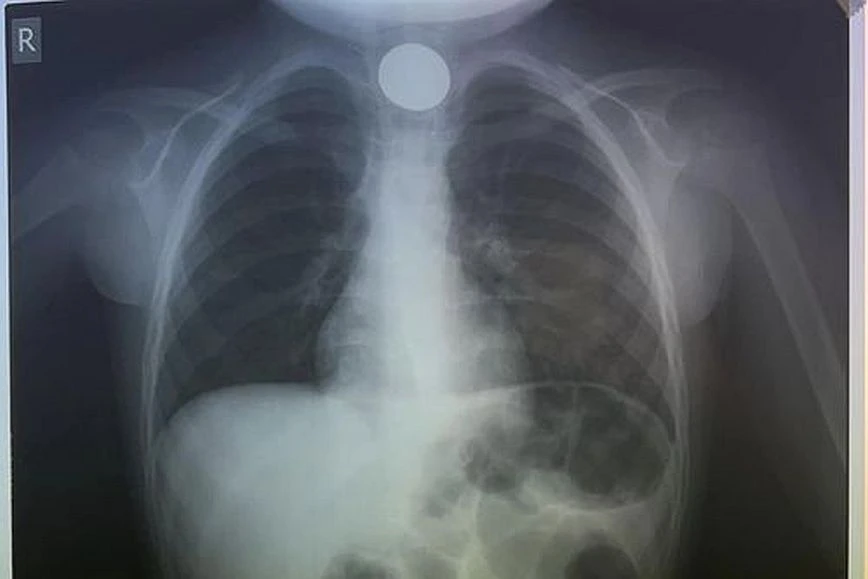

Πιο συγκεκριμένα, ο μικρός κάτω από αδιευκρίνιστες συνθήκες κατάπιε κατά λάθος ένα κέρμα και όταν οι γονείς του αντιλήφθηκαν τι είχε συμβεί έσπευσαν να το μεταφέρουν στο νοσοκομείο. Το παιδί δυσκολευόταν μεν να αναπνεύσει, αλλά ευτυχώς είχε τις αισθήσεις του. Όταν έφτασαν στο ΠΑΓΝΗ, η πρώτη κίνηση των γιατρών ήταν να του κάνουν ακτινογραφία, για να δουν σε ποιο σημείο ακριβώς είχε σταθεί το νόμισμα και αμέσως μετά προχώρησαν στη διαδικασία αφαίρεσής του. Δεν πέρασε πολύς χρόνος και οι γιατροί κατάφεραν να αντιμετωπίσουν επιτυχώς το επείγον περιστατικό, λύνοντας ταχύτατα το πρόβλημα.

Μάλιστα σε σχετική ανάρτηση της Ωτορινολαρυγγολογικής Κλινικής του νοσοκομείου αναφέρεται το περιστατικό μαζί με ευχές για μια καλή χρονιά: «Αποχαιρετάμε το 2023 με επείγουσα αφαίρεση σε κατάποση κέρματος σε 4χρονο. Καλή Χρονιά».